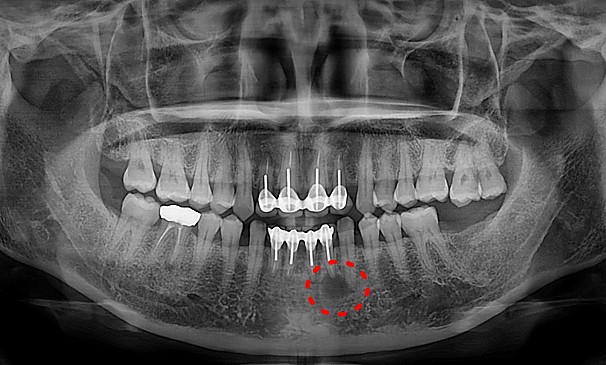

뿌리염증 제거술란?

치아 뿌리 끝에 염증이 생긴 경우는 몇 가지의 원인이 있습니다. 교합문제나 다른 자연 발생적으로 생긴 염증일 수 있고,

이미 신경 치료된 치아가 어떤 이유에서 다시 감염 되었을 때도 뿌리에 염증이 생길 수 있습니다. 염증이 생긴 원인과 염증 범위에 따라 여러 가지 형태로 치료할 수 있습니다.

뿌리염증 제거술